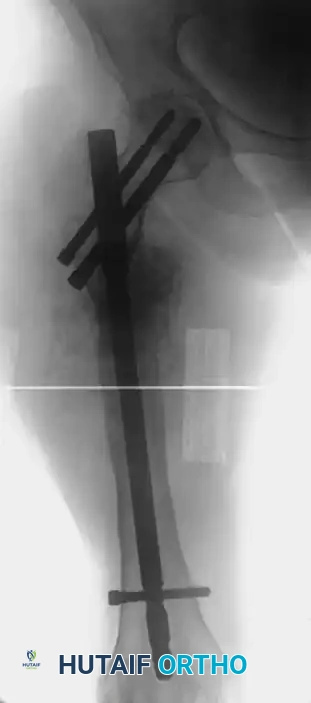

Image

FIGURE 59-10B: Postoperative appearance of the same patient treated with a locked second-generation cephalomedullary femoral nail, achieving robust mechanical alignment and stabilization.